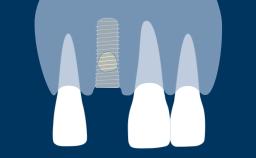

A osteotomia do implante é uma etapa cirúrgica essencial na implantodontia. Termina com a inserção de um implante dentário que posteriormente fornecerá ao paciente um substituto fixo ou removível para a ausência de dentes. Neste módulo, descreveremos primeiro a técnica correta de preparação óssea para a instalação do implante. Posteriormente, abordaremos os ajustes do protocolo necessários em diferentes densidades ósseas. Finalmente, discutiremos os riscos potenciais associados à técnicas inadequadas de osteotomia.

- definir a sequência, velocidade e técnica de perfuração e reconhecer sua relação com a estabilidade primária do implante e a osseointegração